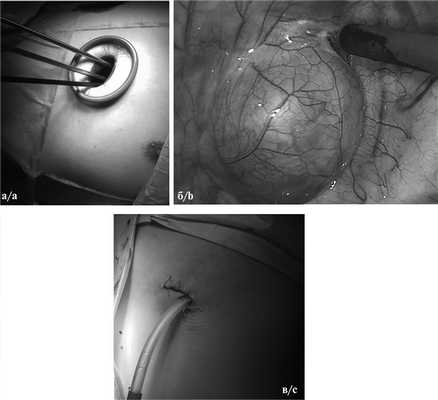

При однопортовом доступе выполняли единственный 3—4 см разрез кожи и мягких тканей (как правило, в 4-м или 5-м межреберье по задней подмышечной линии), через который осуществляли манипуляции, удаление опухоли и последующее дренирование (рис. 1).

Рис. 1. Интраоперационные фотографии унипортального доступа.

а — общий вид операционной раны; б — паравертебральная опухоль; в — вид раны после операции.